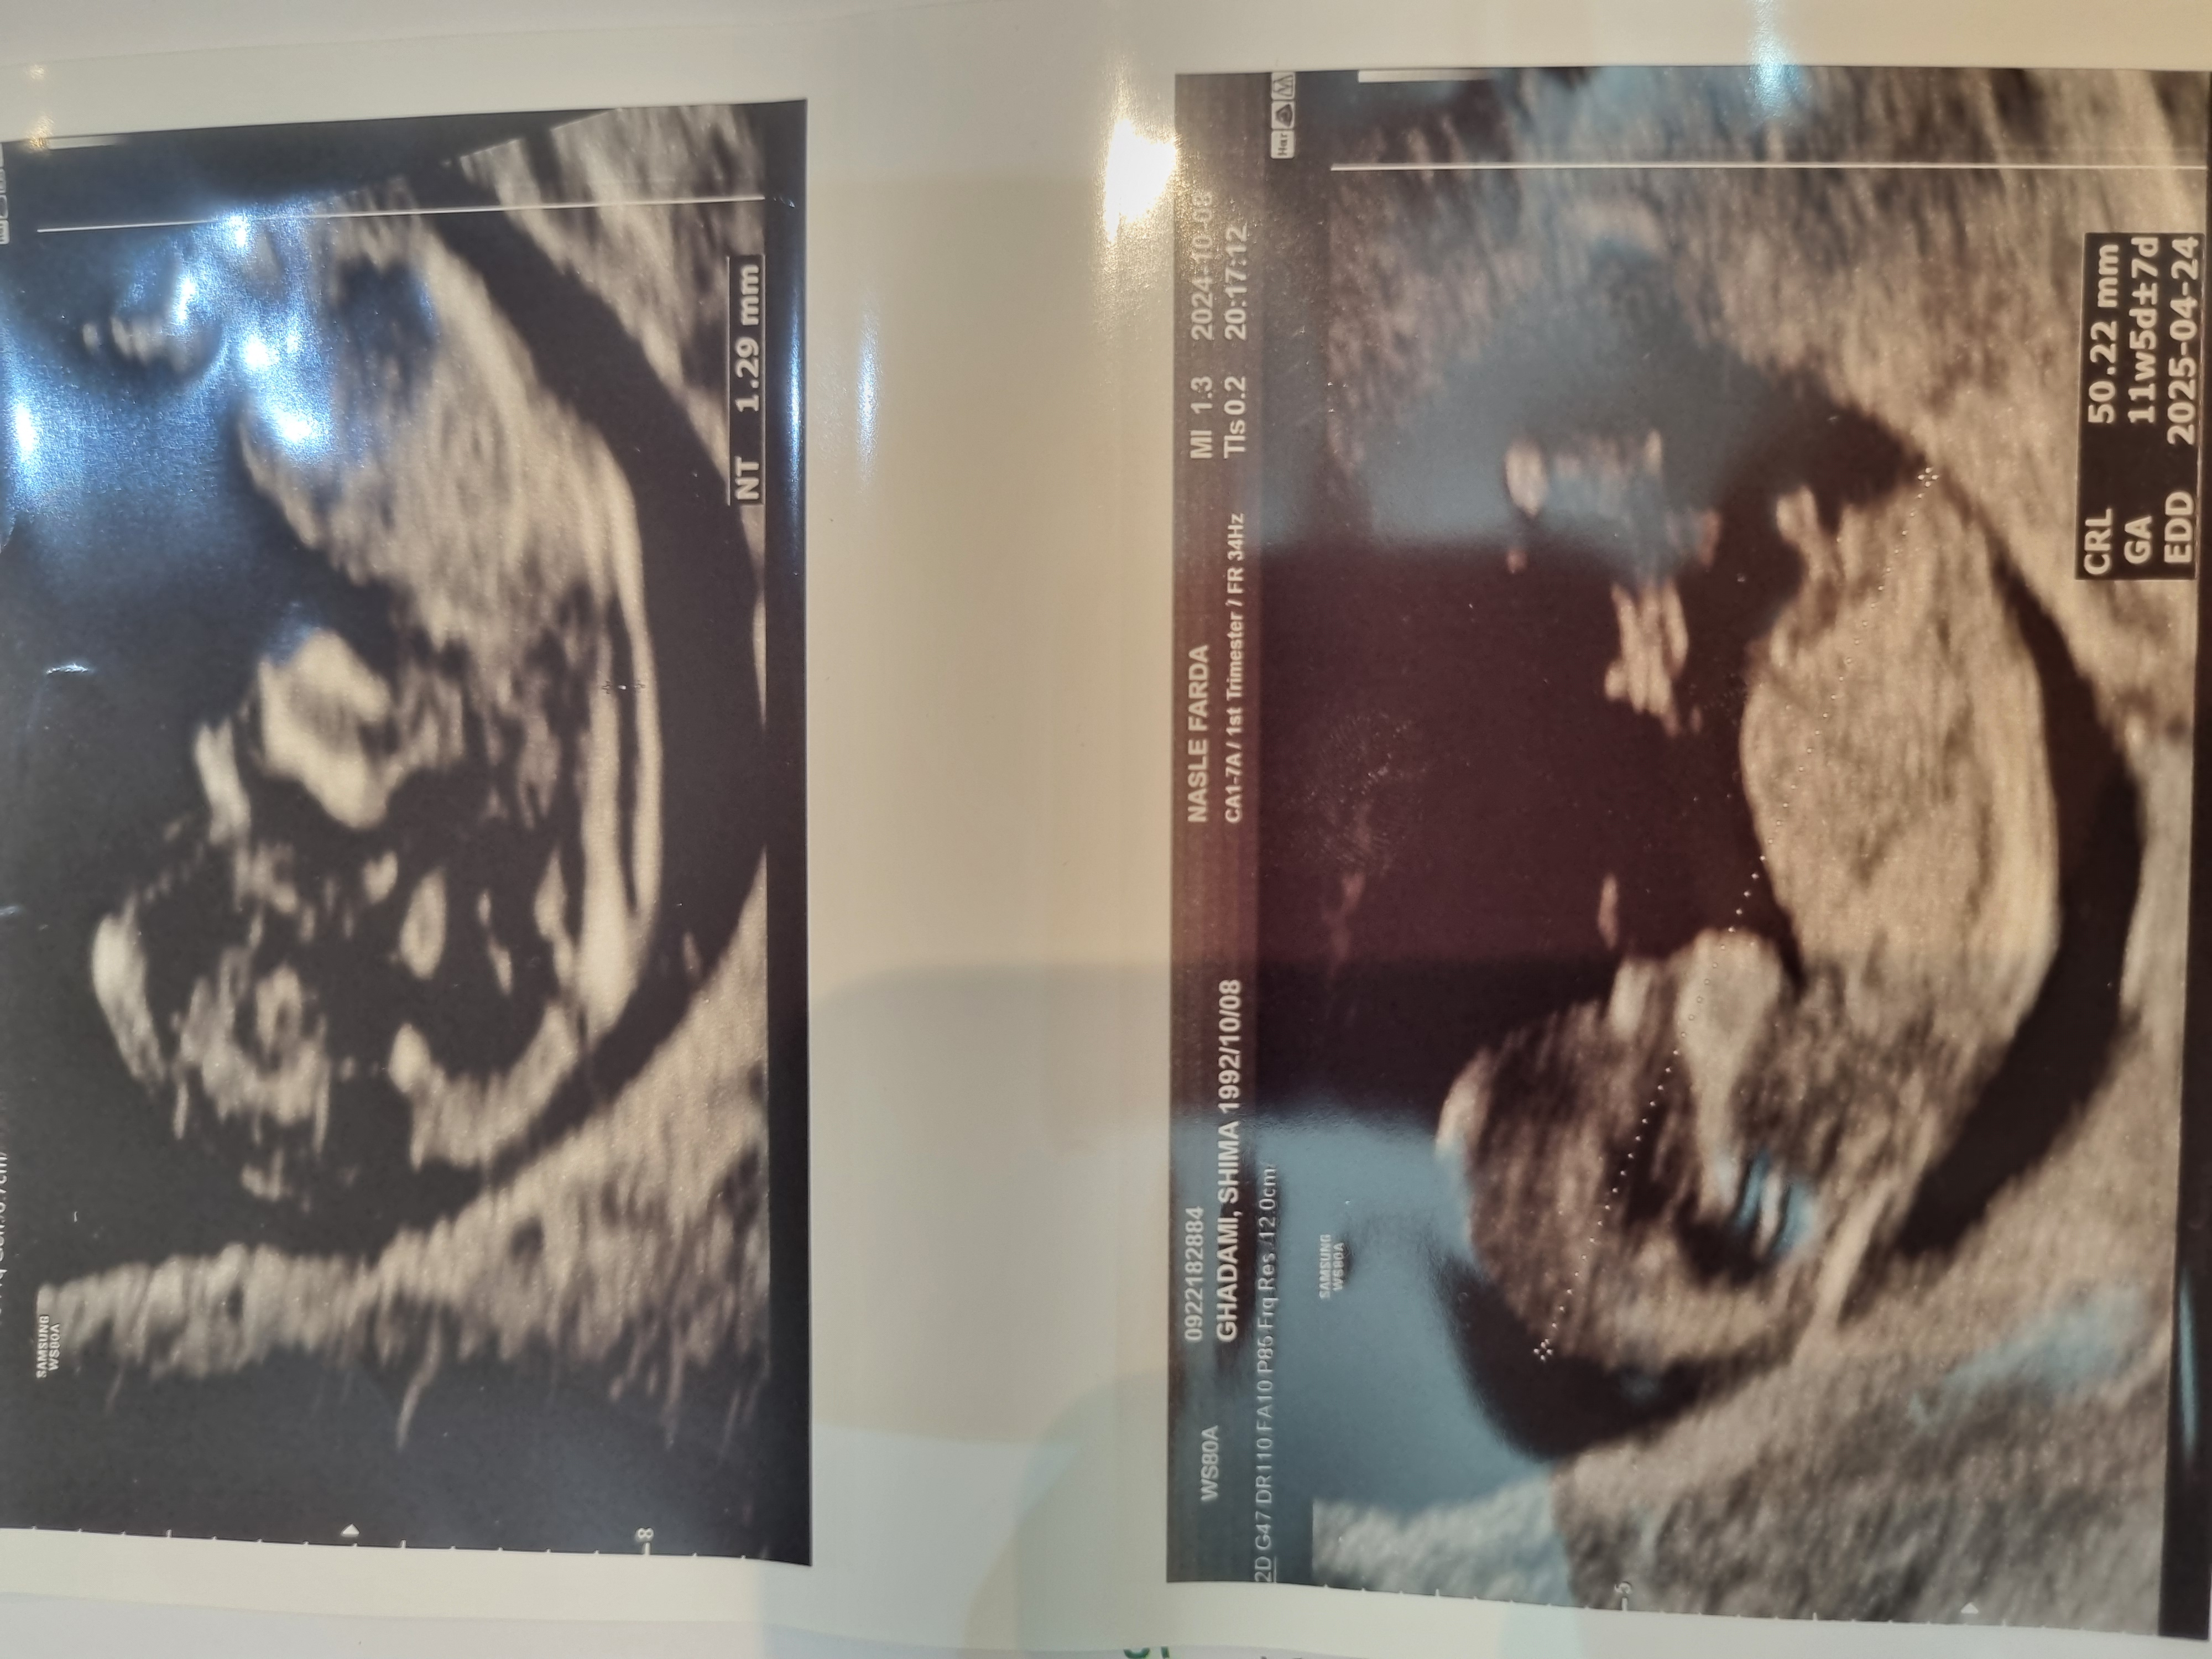

الان بارداره من فکر میکنم 5 ماه یا 4 ماه هست

من میدونم الان همه جنسیت رو میدونن و از رفتار ها هم مشخصه بچشون پسره